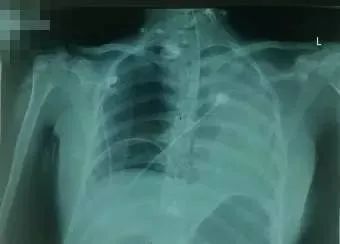

当日复查胸片(图2),再经床旁超声证实左侧大量胸腔积液,行左侧胸腔积液引流,共引流620ml。

图2?本胸片仅确诊左侧胸腔积液,未注意气管插管深度